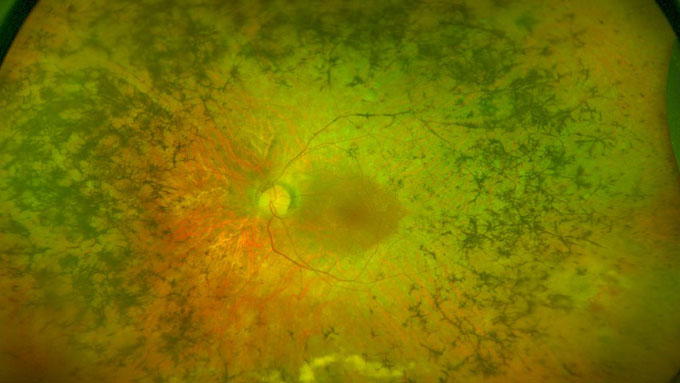

La retinosis pigmentaria es una degeneración hereditaria de la retina que, en función del gen responsable, puede tener una progresión más o menos severa.

Pese a su condición minoritaria, la retinosis pigmentaria es la enfermedad hereditaria más frecuente de la retina y afecta aproximadamente a 1 de cada 4.000 personas. Producida por una degeneración de las células fotorreceptoras (los conos y los bastones), esta distrofia retiniana provoca una pérdida progresiva de la visión periférica y ceguera nocturna, así como deslumbramientos y cataratas en estadios más avanzados. Aunque carece de tratamiento, su gravedad –variable en función del gen afectado que da lugar a la patología–, ha motivado el desarrollo de diferentes líneas de estudio, como la que se está llevando a cabo, con importantes hallazgos, desde el laboratorio de biología molecular de IMO.